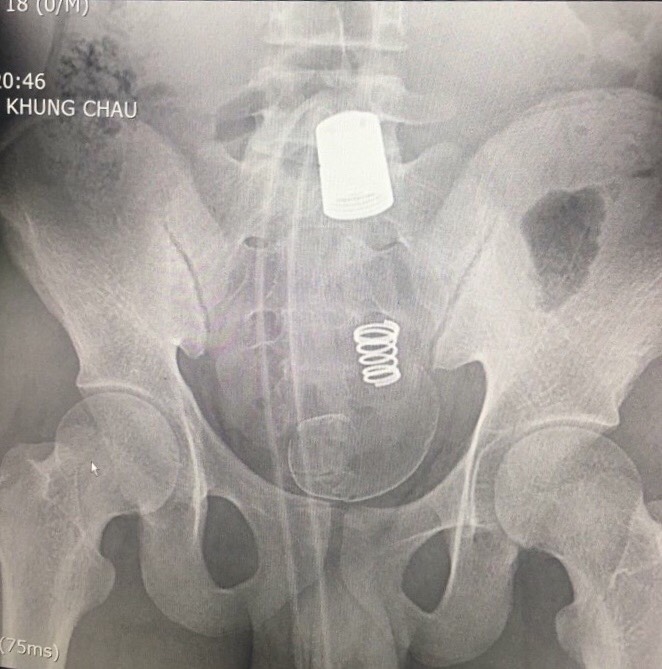

Ngay khi bệnh nhân nhập viện, các bác sĩ đã phát hiện trên phim chụp X-quang có hình ảnh dị vật cản quang rất lớn trong ổ bụng. Qua hỏi bệnh và thăm khám bệnh nhân kể khi đi đại tiện sử dụng vòi xịt vệ sinh, trong quá trình xịt rửa, phần hậu môn co thắt làm vòi xịt đi sâu vào hậu môn trực tràng không kéo lại được. Bệnh nhân tự dùng dao cắt rời đoạn vòi nước và đến viện ngay sau đó. Tiến hành thăm khám hậu môn các bác sỹ phát hiện có dị vật hình ống silicon, rất chắc, không lấy được qua đường hậu môn, có chảy máu niêm mạc đường ruột. Trường hợp dị vật đại trực tràng lớn như trên rất hiếm gặp, không thể tự đại tiện ra được và gây hậu quả rất nghiêm trọng như tắc ruột, vỡ ruột nguy hiểm đến tính mạng nếu không được xử trí sớm.

X-quang: Hình ảnh dị vật cản quang lớn trong ổ bụng |  Đầu dị vật thò ra ngoài lỗ hậu môn |